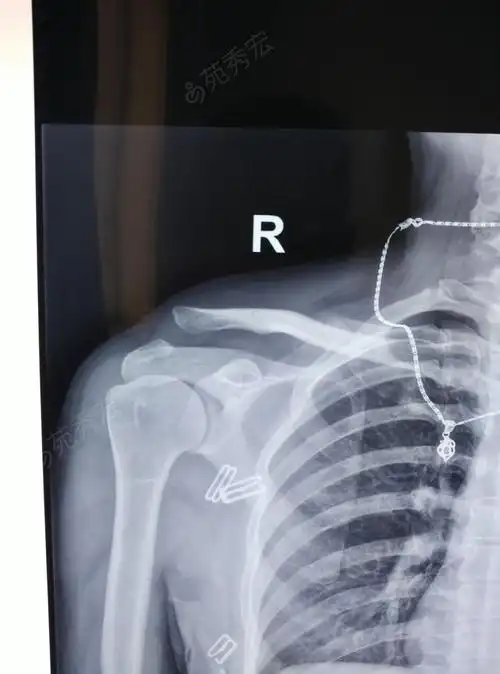

左肩锁关节脱位及复位后

常规肩锁关节脱位锁骨钩没啥技巧

肩锁关节脱位

外伤后头晕头痛伴左肩部疼痛左肩锁关节脱位一例